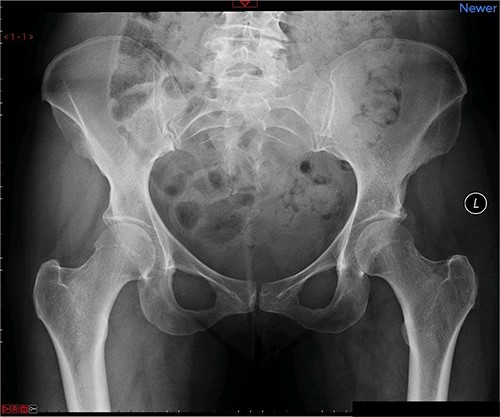

A magnetic resonance imaging (MRI) scan performed in October 2013 (Fig. 1) identified non-compressive, degenerated discs at L4/5 and L5/S1 vertebral levels. However, clinically as the patient was more tender over the left SI joint and the pubic symphysis (Fig. 2), a left sacroiliac joint fusion and symphysis pubis plating procedure was performed in August 2014 (Fig. 3). Following a short period of relief, the pain returned. Subsequently, the patient underwent a 360° fusion (front and back) of the L4/L5 and L5/S1 discs in August 2015 (Fig. 4), a year following the previous surgery. Once again, following a brief period of relief, the symptoms returned. The assumption then was that the initial fusion of the left sacroiliac joint had failed. Therefore, a revision fusion of the left sacroiliac joint and a primary fusion of the right sacroiliac joint was undertaken in August 2017 (Fig. 5).

Postoperative X-ray of the pelvis following the second fusion surgery: postoperative X-ray of the pelvis, performed in January 2016 following the second fusion surgery, showing 360° (front and back) fusion of the L4/5 and L5/S1 disc space.